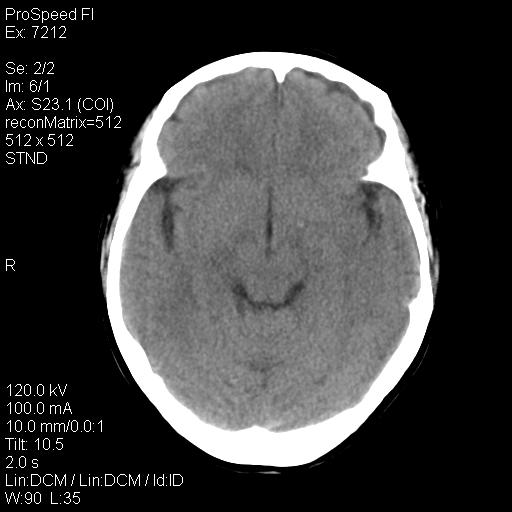

右额叶脑沟变浅,脑表面见新月形稍高密度影,考虑慢性硬膜下出血可能。

左侧额颞部慢性英模下血肿。

1)考虑左侧额部慢性硬膜下血肿(或硬膜下积液)。2)颅骨骨髓瘤不排除;建议行进一步检查。

1)考虑左侧额颞部及右侧额部慢性硬膜下血肿(或硬膜下积液)。2)颅骨骨髓瘤不排除;建议行进一步检查。

考虑左侧额部慢性硬膜下血肿(或硬膜下积液)。

1)右侧半卵圆中心腔隙性脑梗塞。2)考虑左侧额部慢性硬膜下血肿(或硬膜下积液)。3)颅骨骨髓瘤不排除;建议行进一步检查。